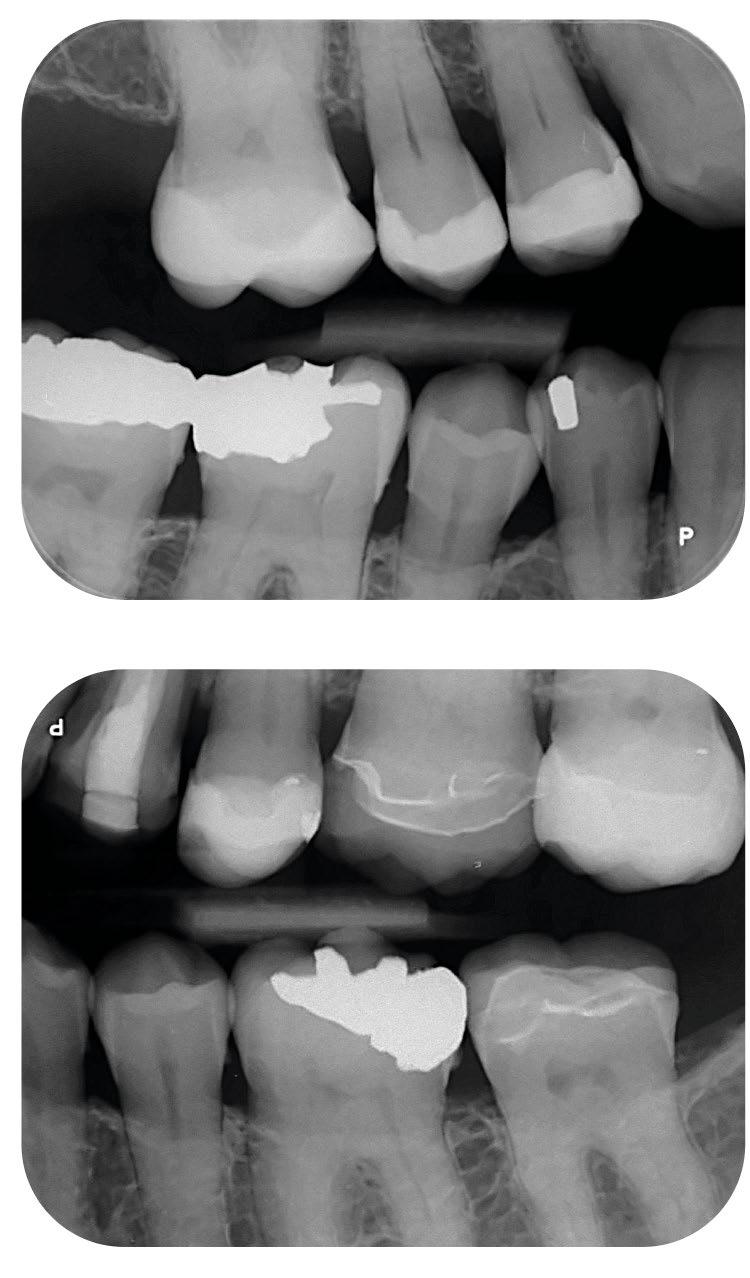

PSPIX2

Fosforplateskanner fra Acteon

PSPIX2 er en lynrask, brukervennlig og meget plassbesparende.

Med sin kompakte størrelse kan den fint plasseres chairside for å forbedre arbeidsflyten og produktiviteten. Kan brukes av opptil 10 arbeidsstasjoner samtidig. Kompatibel med både Windows og Mac.

PSPIX2 er den eneste skanneren på markedet med valgfrie avtakbare deler som kan steriliseres i en autoklav for å gi maksimal beskyttelse.

89.000,2.732,- pr. mnd./3 år

• Oppløsning 20 lp / mm

• Skannetid (hurtigmodus) 1,6s – 2,7s

• Skannetid (toppmodus) 2,1s – 3,6s

• Mål L. 15,4 x D. 20,4 x H. 19,3 cm

• Vekt 2,6 kg